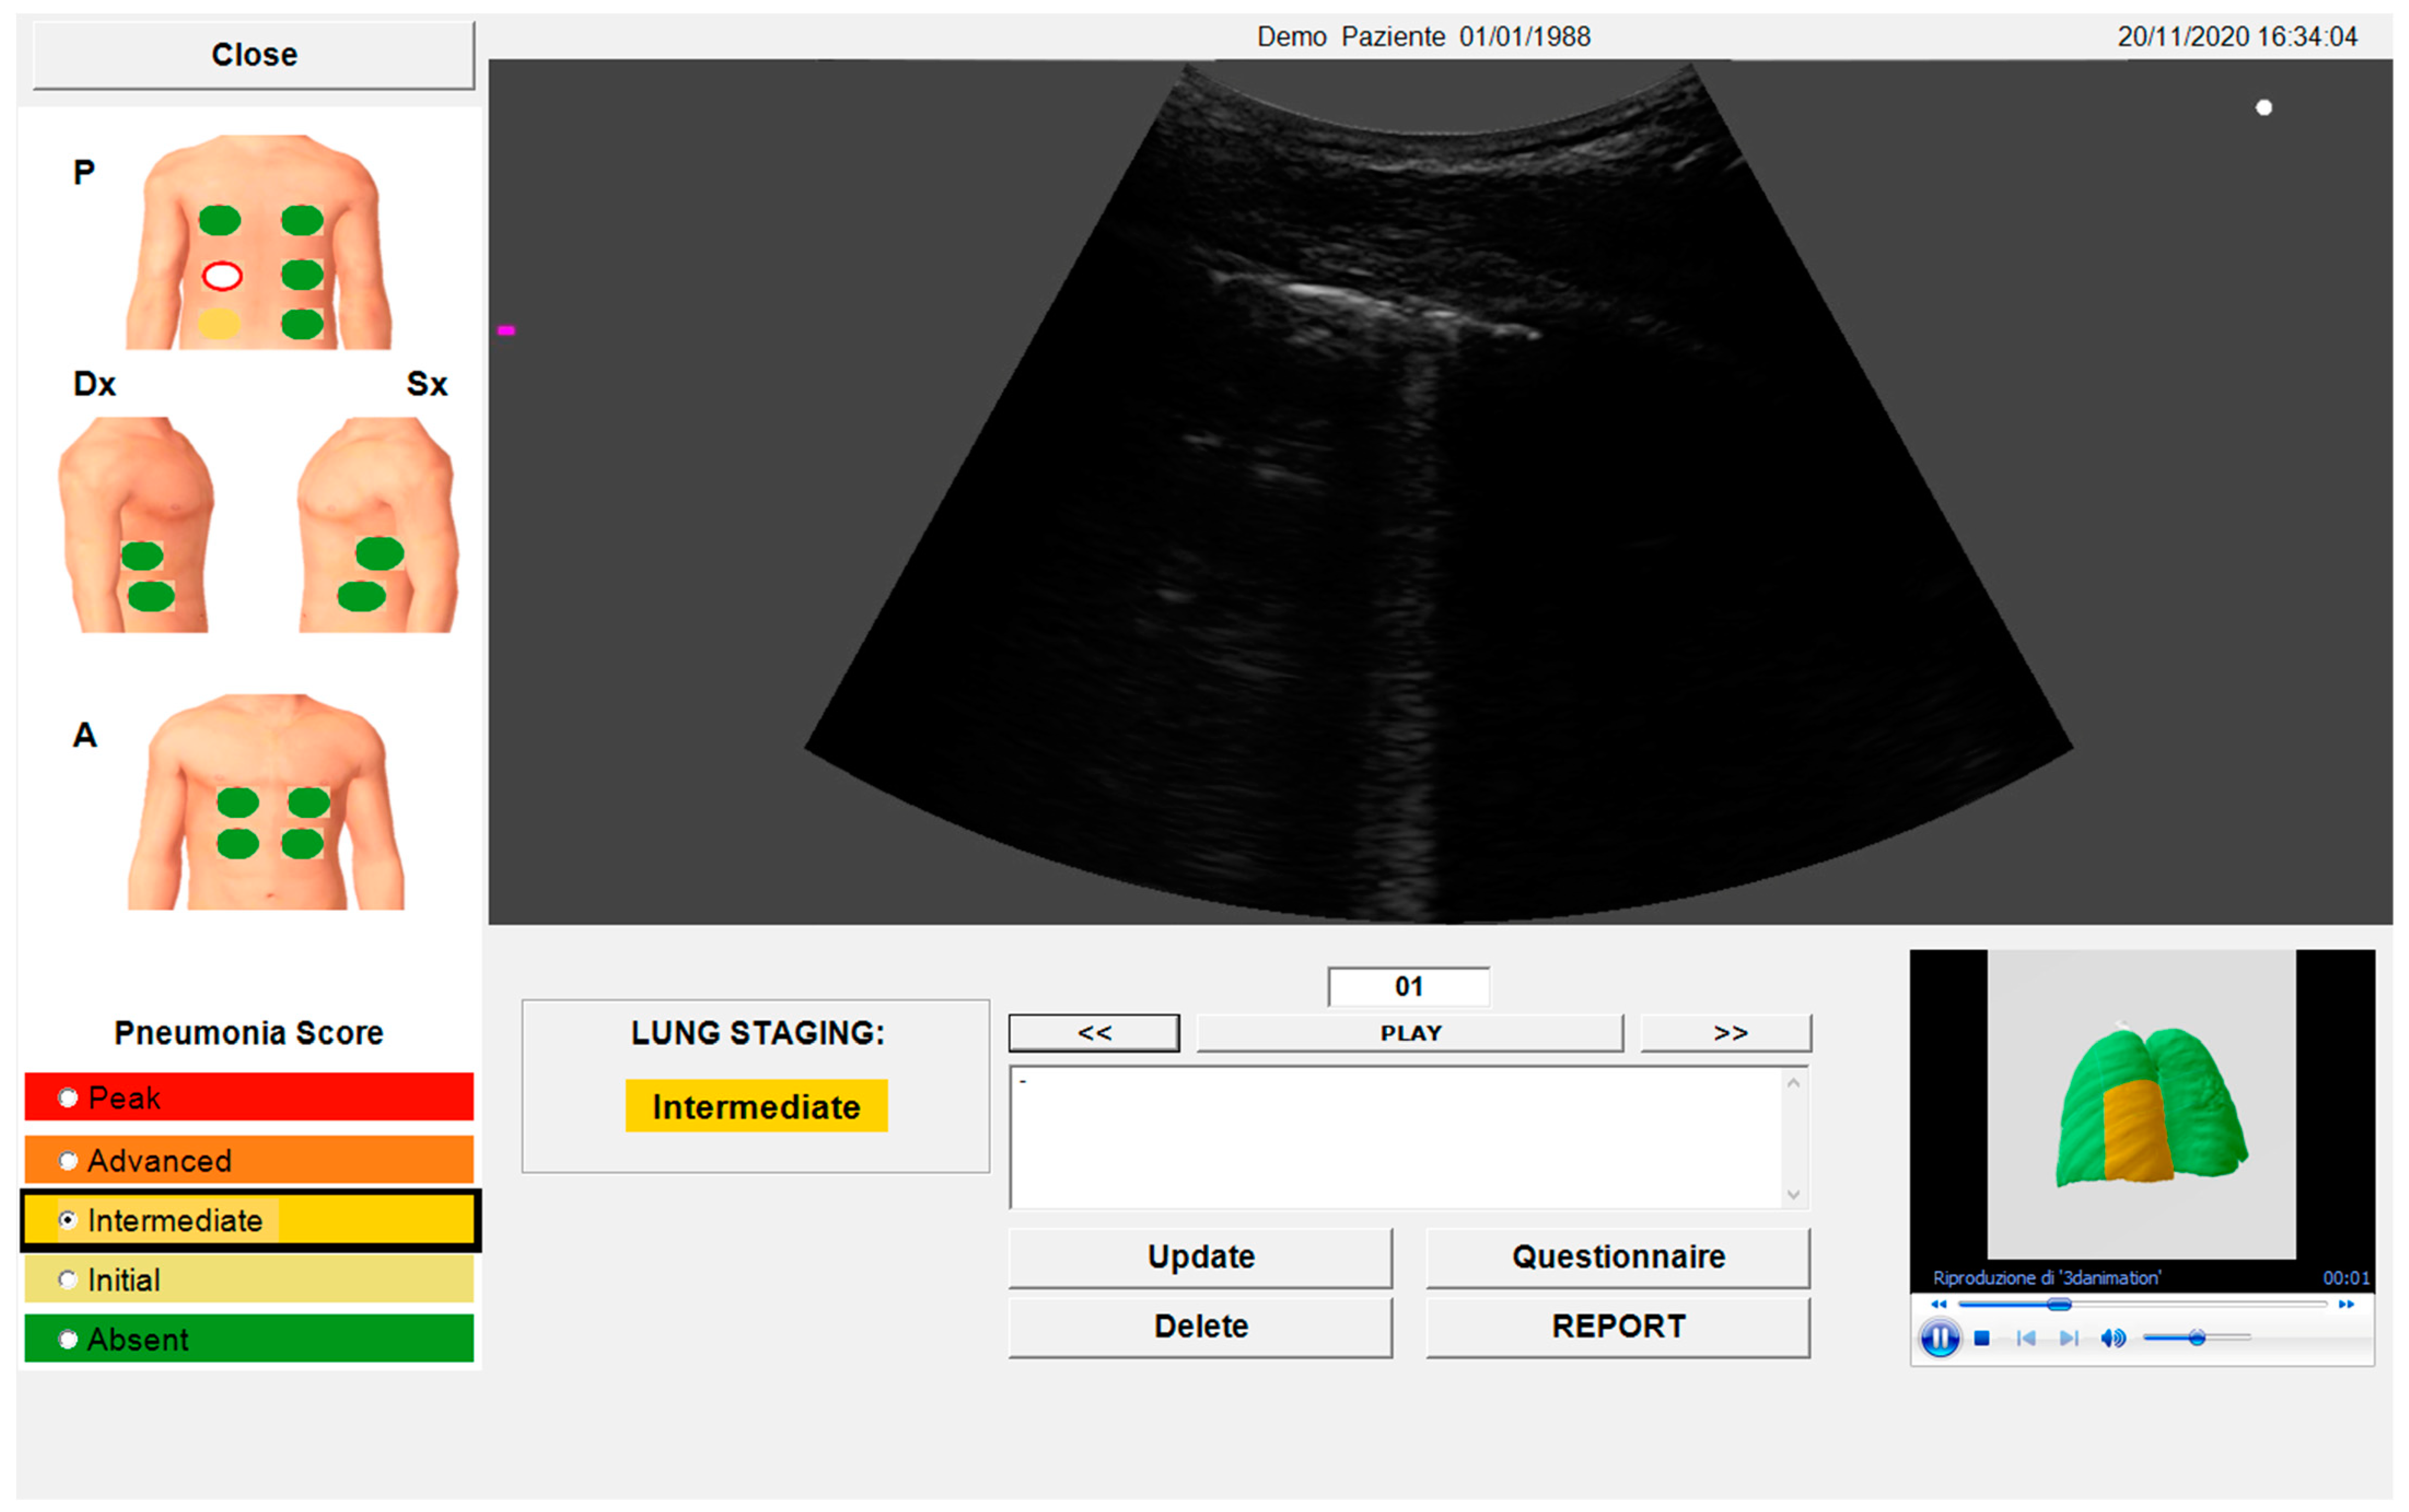

2.4. Automated Algorithm